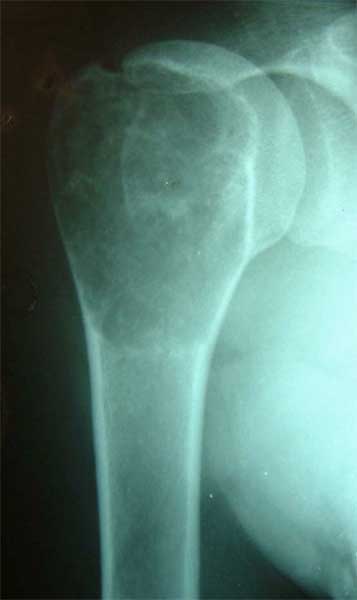

股骨远端骨母细胞瘤               段截肿瘤,大段异体骨移植术后3年,

骨愈合良好,并且获得良好的膝关节功能。